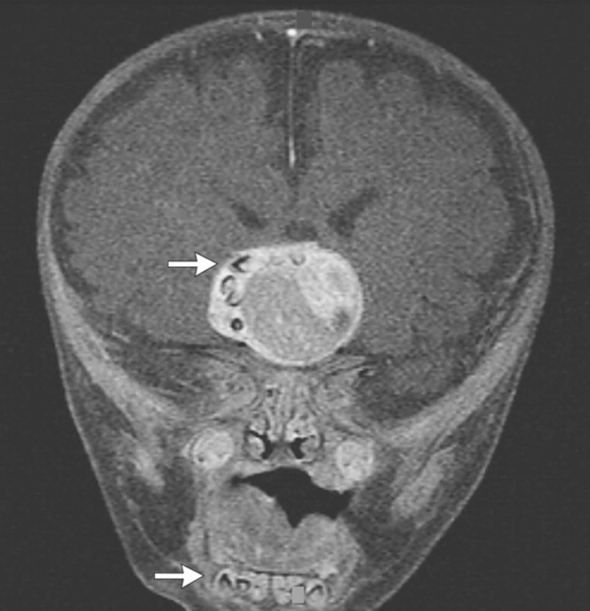

En un primer momento, los médicos se alarmaron cuando notaron que la cabeza del bebé crecía más rápido de lo esperado. Una resonancia magnética (MRI) reveló que tenía un tumor cerca de la hipófisis, dentro del cual se encontraban piezas dentales muy similares a los de la mandíbula inferior.

Dr. Narlin Beaty, neurocirujano en la Universidad de Maryland Medical Center, quien realizó la cirugía del niño, señaló que No todos los días se ven los dientes en cualquier tipo de tumor en el cerebro. En un craneofaringioma, es inaudito.

En el estudio, publicado, los investigadores sostienen que el tumor Craneofaringioma Adamantinomatosa (extirpado quirúrgicamente), surgió de la Bolsa de Rathke, precursor embrionario de una parte de la hipófisis. Esos tumores a veces están rellenos de líquido viscoso de color amarillo que contiene cristales de colesterol. Sin embargo, nunca antes se habían documentado casos con dientes dentro de ellos louis vuitton outlet